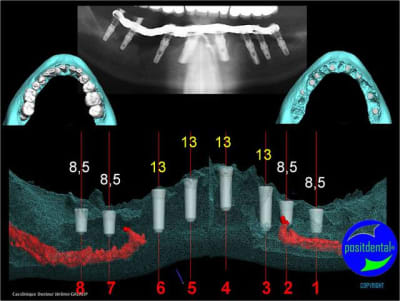

gestion des artéfacts en présence de couronnes

Wax up 3d positdental 8 kt8qmy - Eugenol

Wax up 3d positdental 9 c7cv9z - Eugenol